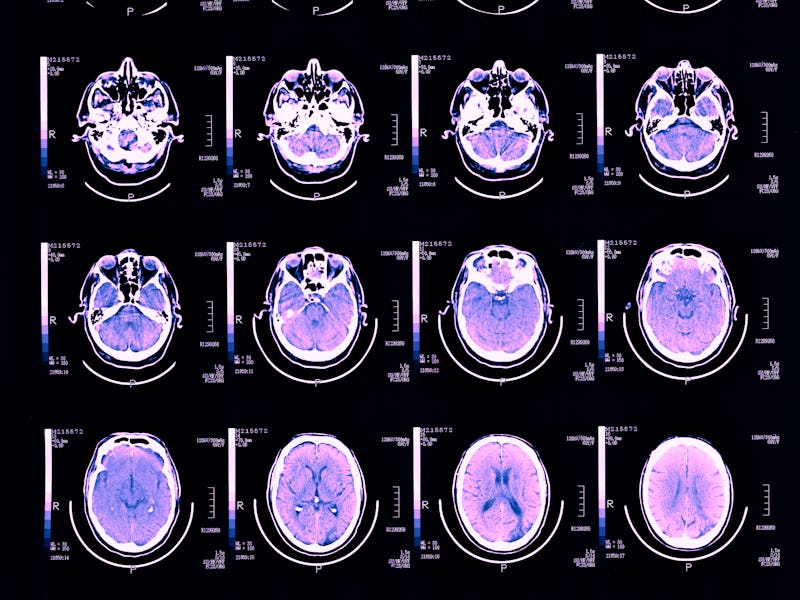

Earlier research suggests that depression-related appetite changes may stem from neural and inflammatory differences between people diagnosed with different kinds of depression. This study, published in August in the journal JAMA Psychiatry, focused on the brain and examined the relationship between appetite changes and the reward system.

Ultimately, scientists found that the direction of appetite changes — an increase or a decrease — matched specific neural alterations. For example, reduced appetite in individuals with depression was associated with weaker communication between the brain’s nucleus accumbens, ventromedial prefrontal cortex, and hippocampus. Meanwhile, increased appetite was linked to weaker communication between the nucleus accumbens and the insular ingestive cortex. The nucleus accumbens is directly involved in motivation and emotion.

What’s more, the scientists found that the more severe an individual’s symptoms, the more robust the neural signature. The changes were so prominent among individuals with severe depression that the team could predict whether or not the study participant experienced an increase or loss of appetite based on their brain.